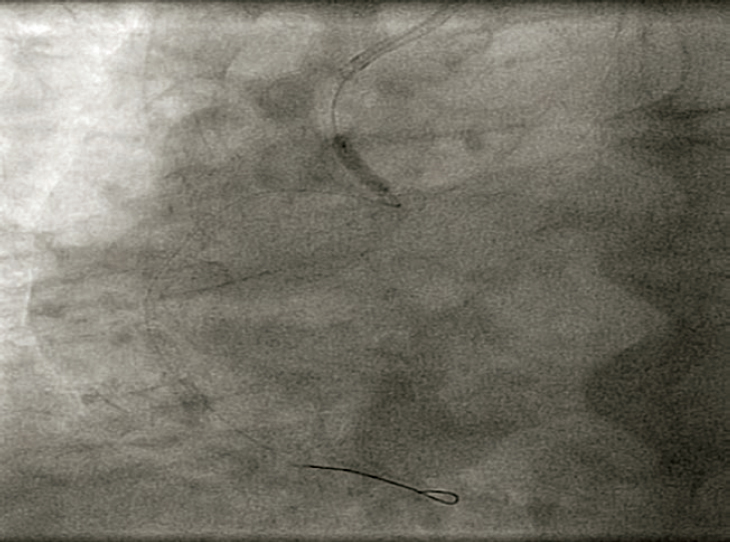

In order to protect the stent from the deformation by the tip of guiding catheter, the Guideliner guiding catheter extension device was used (Vascular Solutions, Inc., Minneapolis, Minnesota, United States). One semi-compliant balloon of 2.5 mm in diameter was advanced towards the proximal segment of the right coronary artery where it was inflated. It was then that the Guideliner device was advanced and the inflated balloon was slightly pulled (anchoring) by placing the tip of the guiding catheter extension device into the proximal segment inside the displaced stent (figure 2).

Figure 2. Advancement of the guiding catheter extension device towards the proximal segment of the right coronary artery.